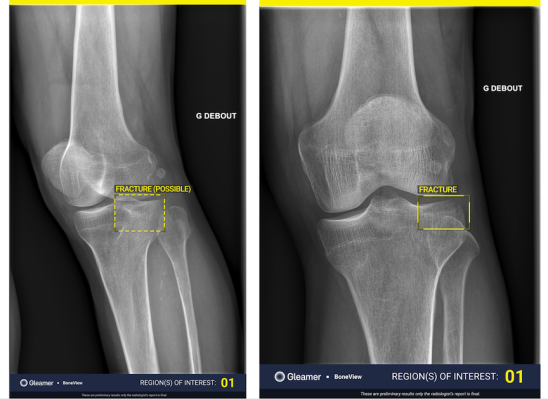

BoneView is a clinical decision support AI-based software solution designed to efficiently identify bone fractures by highlighting areas of interest on an X-ray image, assisting both radiologists and clinicians in their daily practice. This FDA-cleared, computer assisted detection solution (CADe) has been trained on tens of thousands of radiographic images and generated clinical evidence through 80 clinical studies and nearly 25 peer-reviewed scientific publications. It is the only such application that is cleared for use in some pediatric anatomical areas.1 BoneView efficiently highlights fractures and provides confidence levels, such as highlighting 90% as probable. This capability helps boost diagnostic accuracy, reduce radiologist reading times and improve patient care pathways.